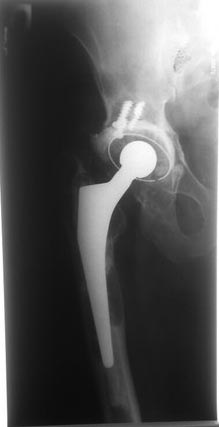

Нестабильна ножка, чашку можно не трогать.